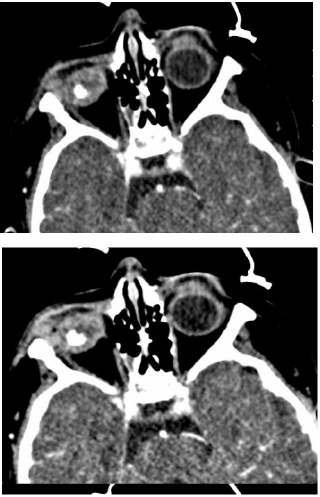

Movie Under the Same Star

Figure 14: a and b CT scan with unilateral retinoblastoma, unilateral, Leukocoria and retinal calcification.